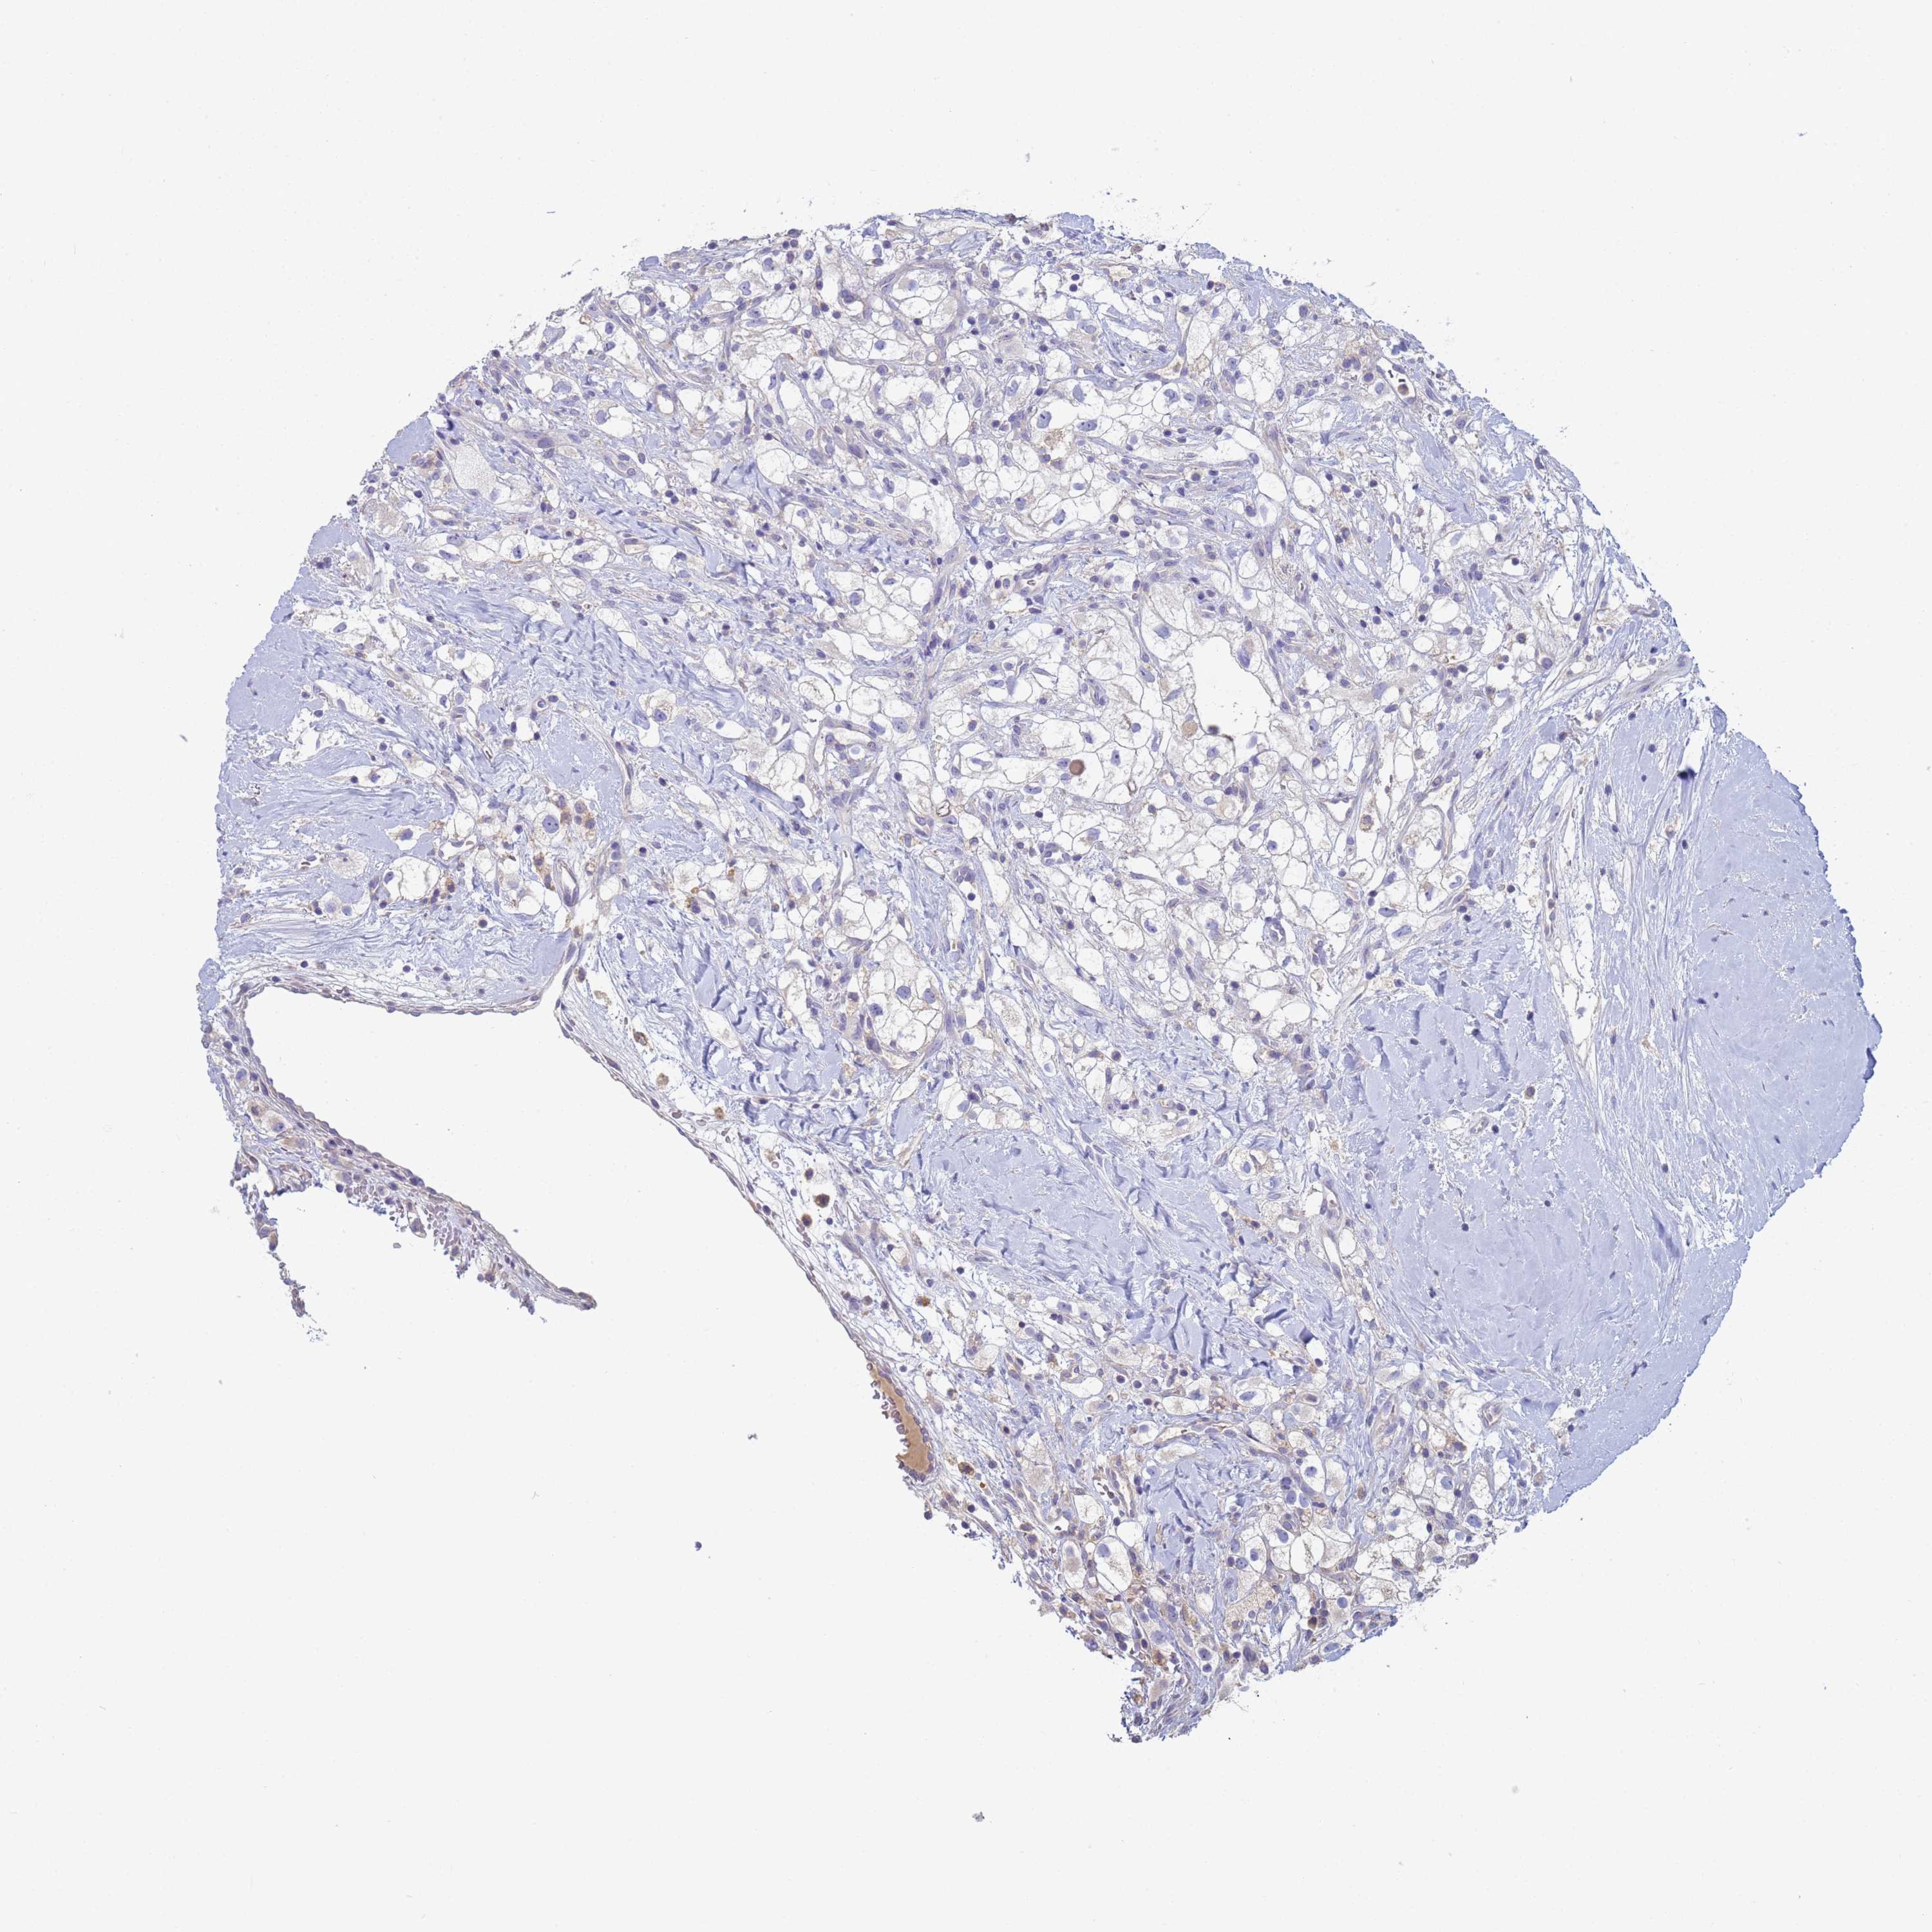

KIDNEY RENAL CLEAR CELL CARCINOMA (VALIDATION) - Interactive survival scatter ploti

The Survival Scatter plot shows the clinical status (i.e. dead or alive) for all individuals in the patient cohort, based on the same data that underlies the corresponding Kaplan-Meier plots. Patients that are alive at last time for follow-up are shown in blue and patients who have died during the study are shown in red.

The x-axis shows the expression levels (FPKM) of the investigated gene in the tumor tissue at the time of diagnosis. The y-axis shows the follow-up time after diagnosis (years). Both axes are complimented with kernel density curves demonstrating the data density over the axes. The top density plot shows the expression levels (FPKM) distribution among dead (red) and alive patients (blue). The right density plot shows the data density of the survived years of dead patients with high and low expression levels respectively, stratified using the cutoff indicated by the vertical dashed line through the Survival Scatter plot. This cutoff is automatically defined based on the FPKM cutoff that minimizes the p-score. The cutoff can be changed by dragging the vertical line or by entering a cutoff value in the square labeled "Current cut-off".

Under the Survival Scatter plot the p-score landscape (black curve; left axis) is shown together with dead median separation (red curve; right axis). Dead median separation is the difference in median mRNA expression between patients who have died with high and low expression, respectively. It is calculated as follows: median FPKM expression of dead patients with high expression - median FPKM expression of dead patients with low expression. This is intended to aid the user in visually exploring custom cutoffs and the associated p-scores and dead median separation.

Individual patient data is displayed and can be filtered by clicking on one or more of the category buttons on the top of the page. Categories describing expression level and patient information include: high, low, alive, dead, female, male and tumor stages. The scale of the x-axis can be toggled between linear and log-scale by clicking on the "x log" button. Mouse-over function shows TCGA ID, patient information and mRNA expression (FPKM) for each patient.

& Survival analysisi

Kaplan-Meier plots summarize results from analysis of correlation between mRNA expression level and patient survival. Patients were divided based on level of expression into one of the two groups "low" (under cut off) or "high" (over cut off). X-axis shows time for survival (years) and y-axis shows the probability of survival, where 1.0 corresponds to 100 percent.

CR1 is not prognostic in Kidney Renal Clear Cell Carcinoma (validation)

: 1.13

Average pTPM 2.0

Number of samples 100